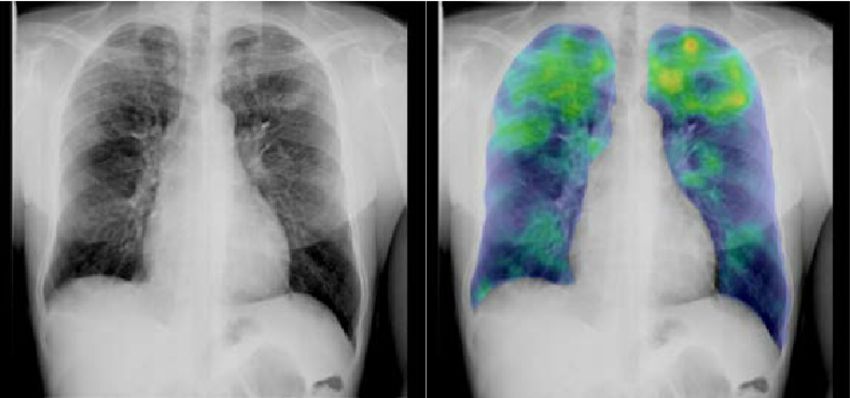

识别图像中的模式(Pattern)是现有人工智能系统中最强有力的一点,研究人员现在正在训练人工智能检查胸部x光片,识别结核病。这项技术可以为缺乏放射学家的结核病流行地区带来有效的筛查和评估手段。

用于检测和诊断癌症的传统方法包括计算机断层扫描( CT )、磁共振成像( MRI )、超声和X射线。不幸的是,许多癌症无法通过这些技术得到足够准确的诊断,从而可靠地挽救生命。微阵列基因图谱的分析是一种替代方法,但这项技术需要计算很多小时,除非这项技术可以使用AI替换。现在已经被证明,斯坦福大学的人工智能诊断算法与由21名经委员会认证的皮肤科医生的团队一样有效地从图像中检测潜在的皮肤癌。Startup Enlitic正在使用深度学习来检测CT图像中的肺癌结节,其算法比作为一个团队工作的专家胸科医生的准确率高50%。